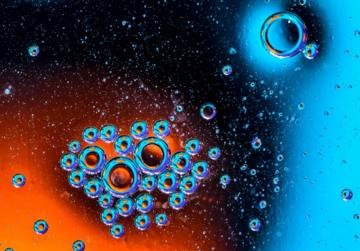

Khi sử dụng một thiết bị bên ngoài để phát sóng siêu âm, các giọt chất này tạo ra các quả bong bóng có kích cỡ lớn dần lên và nó sẽ làm tắc nghẽn các mạch máu.

Khi họ tiến hành siêu âm, họ phát hiện ra rằng những giọt nước đã tạo thành các quả bong bóng dính khít với nhau, có một vài quả trong số chúng kết hợp tạo ra các bong bóng có kích cỡ lớn hơn, và sau đó làm nghẽn các mạch máu nhỏ hoặc các mao mạch của mô.

Họ cũng quan sát thấy những quả bóng này xâm nhập vào bên trong mạch máu và làm cho mạch máu bị vỡ ra.